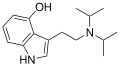

| Wzór sumaryczny |

C16H24N2O | ||||||||

4-Hydroksy-N,N-diizopropylotryptamina – psychodeliczna substancja psychoaktywna z rodziny tryptamin.